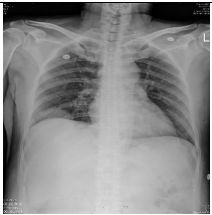

15. 39y/o Female, progressive dyspnea and chest tightness for several days